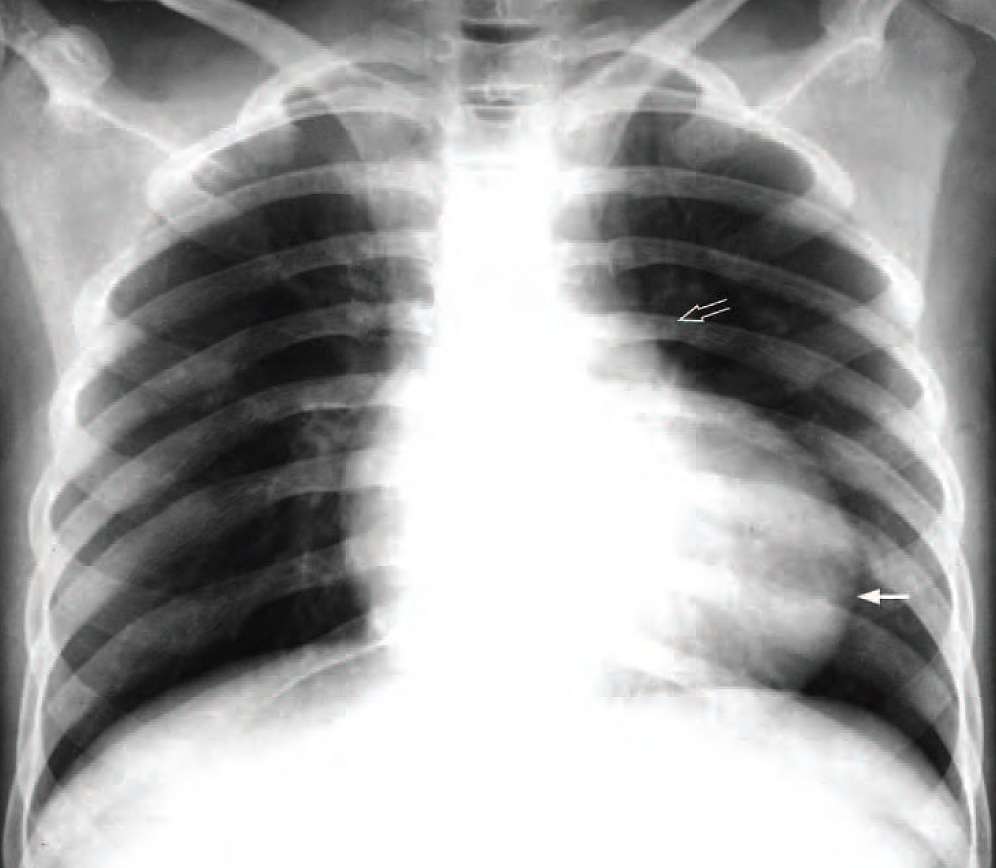

2-year-old child presented with shortness of breath on playing and multiple short episodes of loss of consciousness. On examination the child was cyanotic and a heart murmur was noted. A CXR was performed as an initial examination.

What are the CXR findings and what is the most likely diagnosis ?